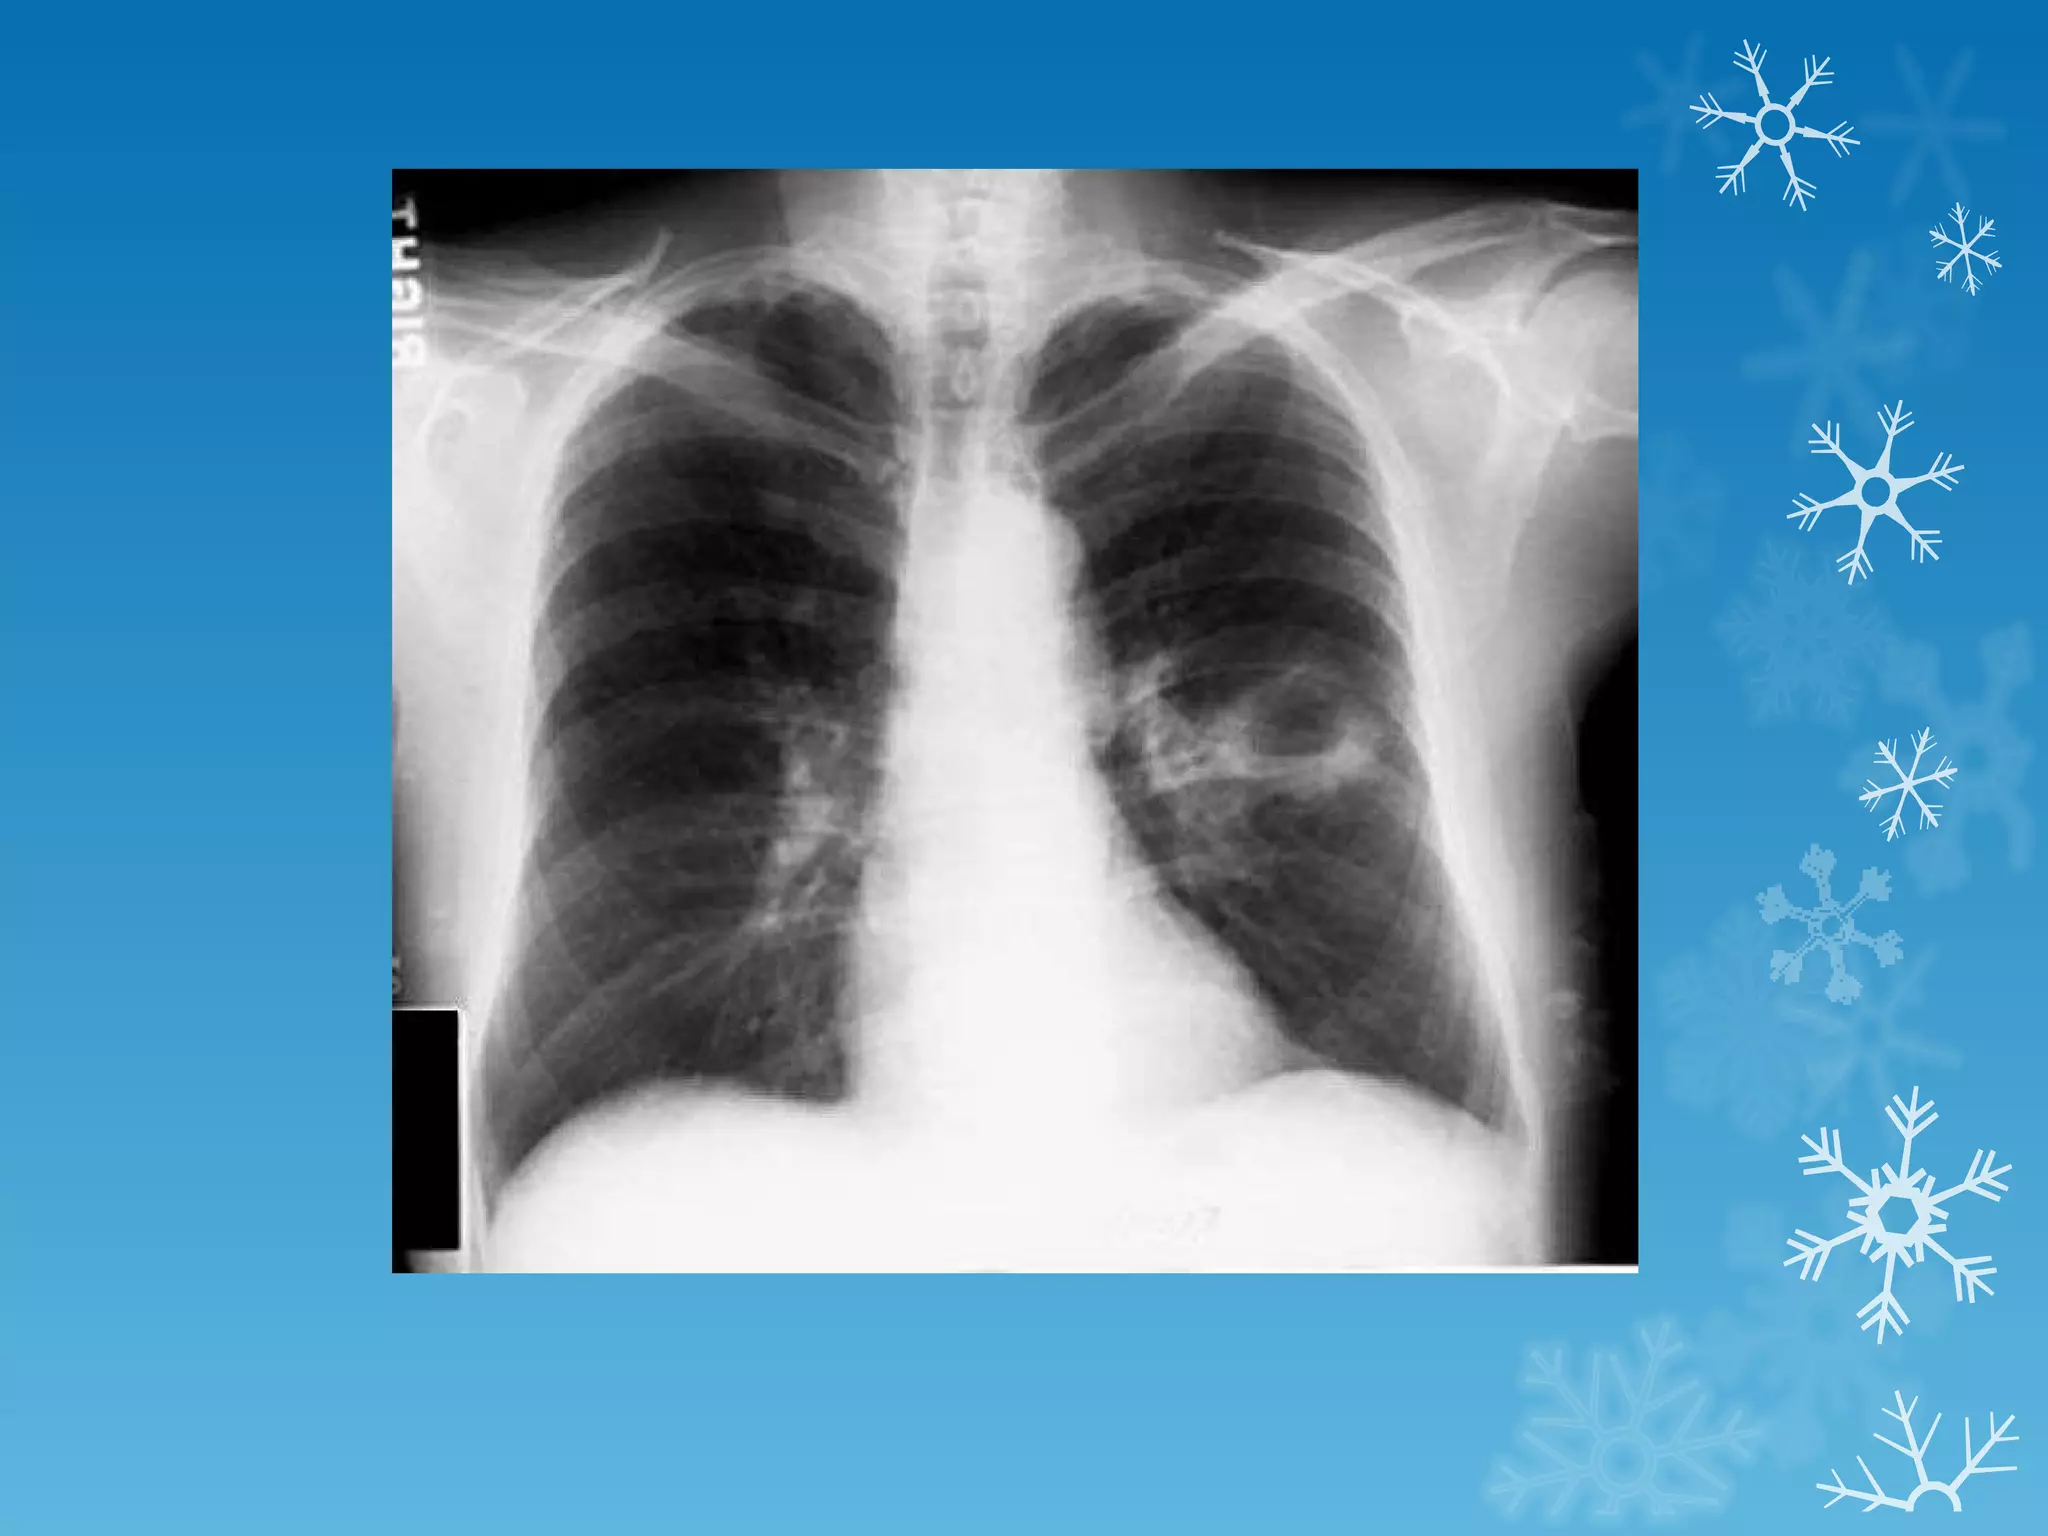

This document discusses chest x-ray interpretation and provides guidance on evaluating x-rays. It explains that tissue density determines how an x-ray beam penetrates, with denser tissues appearing whiter and less dense tissues appearing blacker. It also outlines different chest x-ray views and factors to consider like patient orientation, age, gender, and rotation. Abnormalities are described as appearing too white, too black, too large, or in the wrong place. The document stresses a systematic approach of identifying, localizing, describing lesions, and providing differential diagnoses.